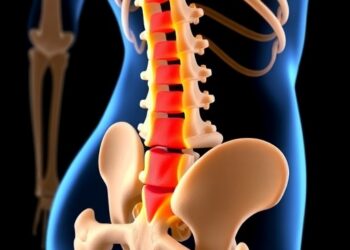

Investigating deeper into this connection, the researchers identified the basolateral amygdala (BLA) in the brain, which plays a pivotal role in processing emotions such as fear and anxiety. Their studies suggested that heightened activity in the BLA was closely linked to the absence of beneficial microbes. This phenomenon was attributable to calcium-dependent SK2 channels within brain cells, which are implicated in modulating anxiety-related behavior. Under normal conditions where the system is exposed to live microbial metabolites, these SK2 channels function effectively to prevent neurons from excessive excitation, stabilizing emotional responses.

The research team, led by Associate Professor Shawn Je, delved further into the impact of reintroducing live microbes into germ-free mice. The results were compelling: the introduction of microbial populations resulted in a substantial decrease in neuronal hyperactivity in the BLA. Consequently, these mice exhibited much lower levels of anxiety-related behavior, aligning their emotional responses with those of mice that had an established microbial community.

Additionally, the team explored the therapeutic potential of indoles, the specific metabolites produced by certain gut microbes. Germ-free mice that received indole treatment showed a marked reduction in BLA activity and exhibited less anxiety-related behavior. This crucial observation reinforces the hypothesis that our indigenous microbiota could significantly influence our emotional well-being through the production of beneficial metabolites.